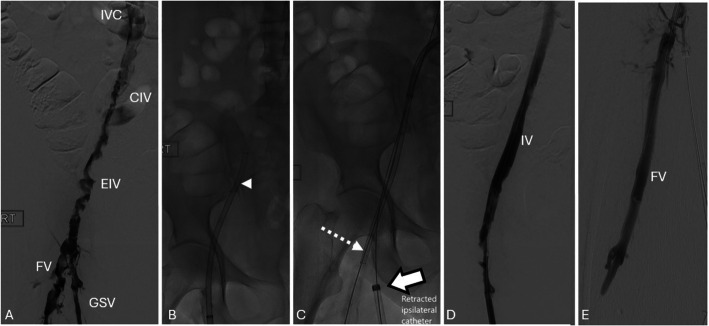

Abstract Image